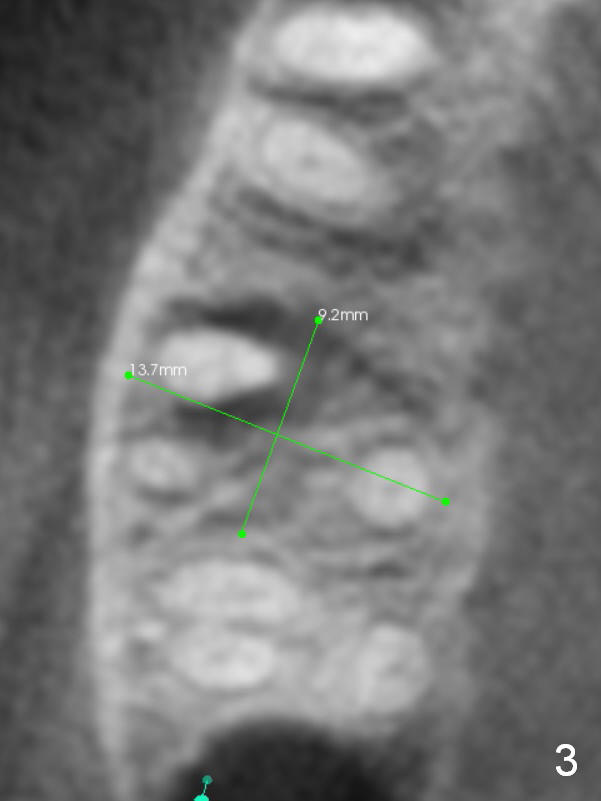

A 52-year-old lady (ZJ) has severe bone loss at #3 (Fig.1 (CT sagittal section)). After extraction, the socket will be treated with Metronidazole. A small amount of apical bone is available for primary stability; the bone density is also low (300-500 Hounsfield Units, Fig.3 (axial section)). Use RT2,3 for creating osteotomy and bone condensation, followed by 4.5-7x14 mm taps (11 mm deep; gingival margin). Prior to bone grafting (Fig.1,2 (coronal section) red circles), apply Endogain against the root surface of the neighboring teeth.